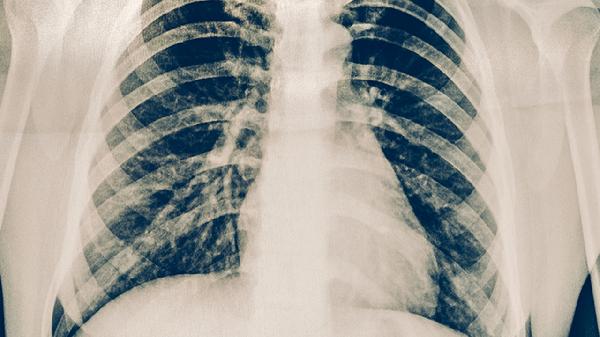

男子一天抽两包烟,一家三口患肺癌,不是耸人听闻

你可能觉得“一人吸烟,全家遭殃”是危言耸听,但现实往往比想象更残酷。一个家庭里,如果有一个“老烟枪”,其他成员的健康风险会直线上升,甚至可能面临同样的疾病威胁。今天,我们就来聊聊二手烟、三手烟对家人的危害,以及如何真正保护你所爱的人。

增加肺癌风险:长期暴露在二手烟环境中,非吸烟者患肺癌的概率提升20%-30%。

医学研究已发现,长期生活在吸烟环境中的非吸烟者,肺癌发病率明显高于无烟家庭。

吸烟者及家人应定期做肺部CT等筛查。